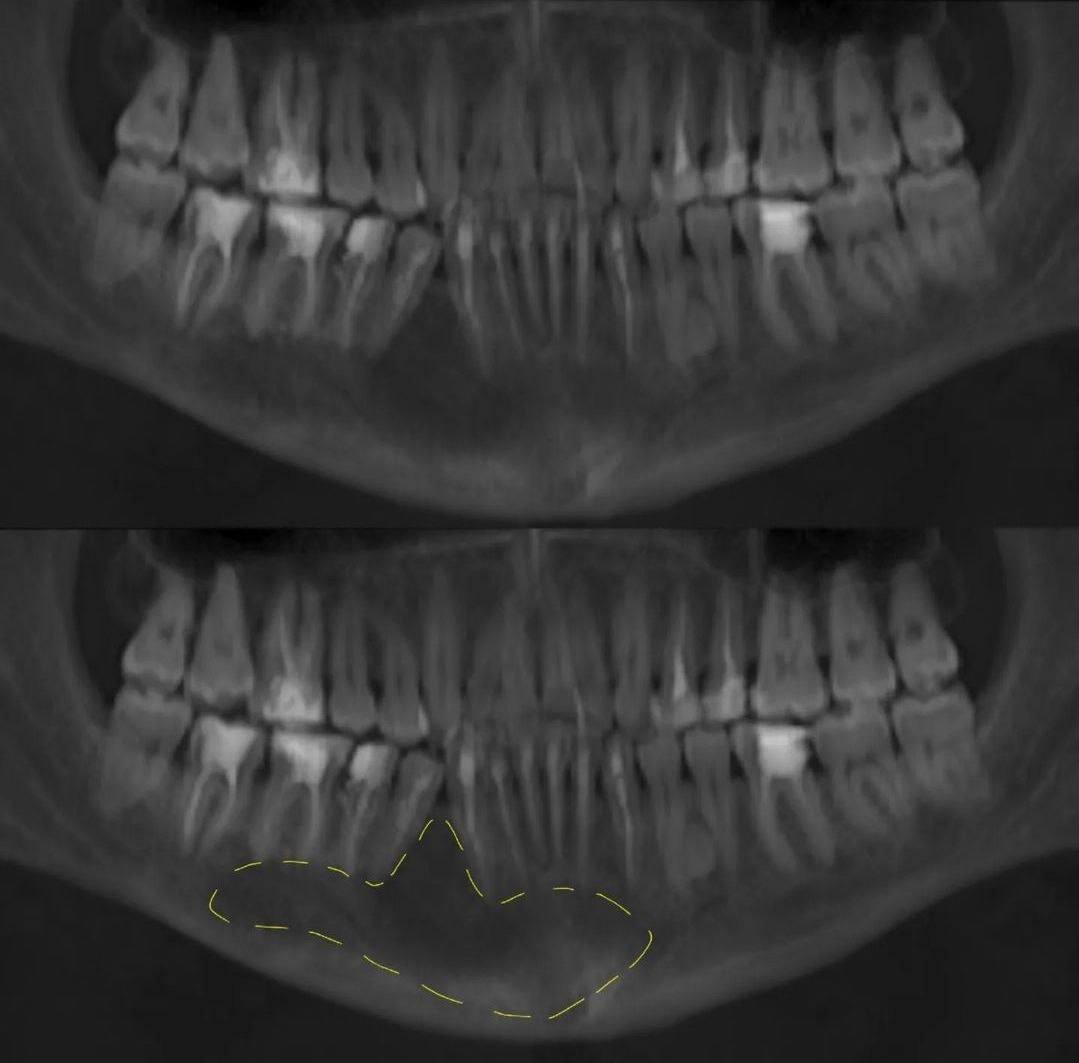

Большинство пациентов не замечают проявления выраженной симптоматики. Опухоль диагностируется случайно при рентгенографии лобной пазухи.

Большинство пациентов не замечают проявления выраженной симптоматики. Опухоль диагностируется случайно при рентгенографии лобной пазухи.